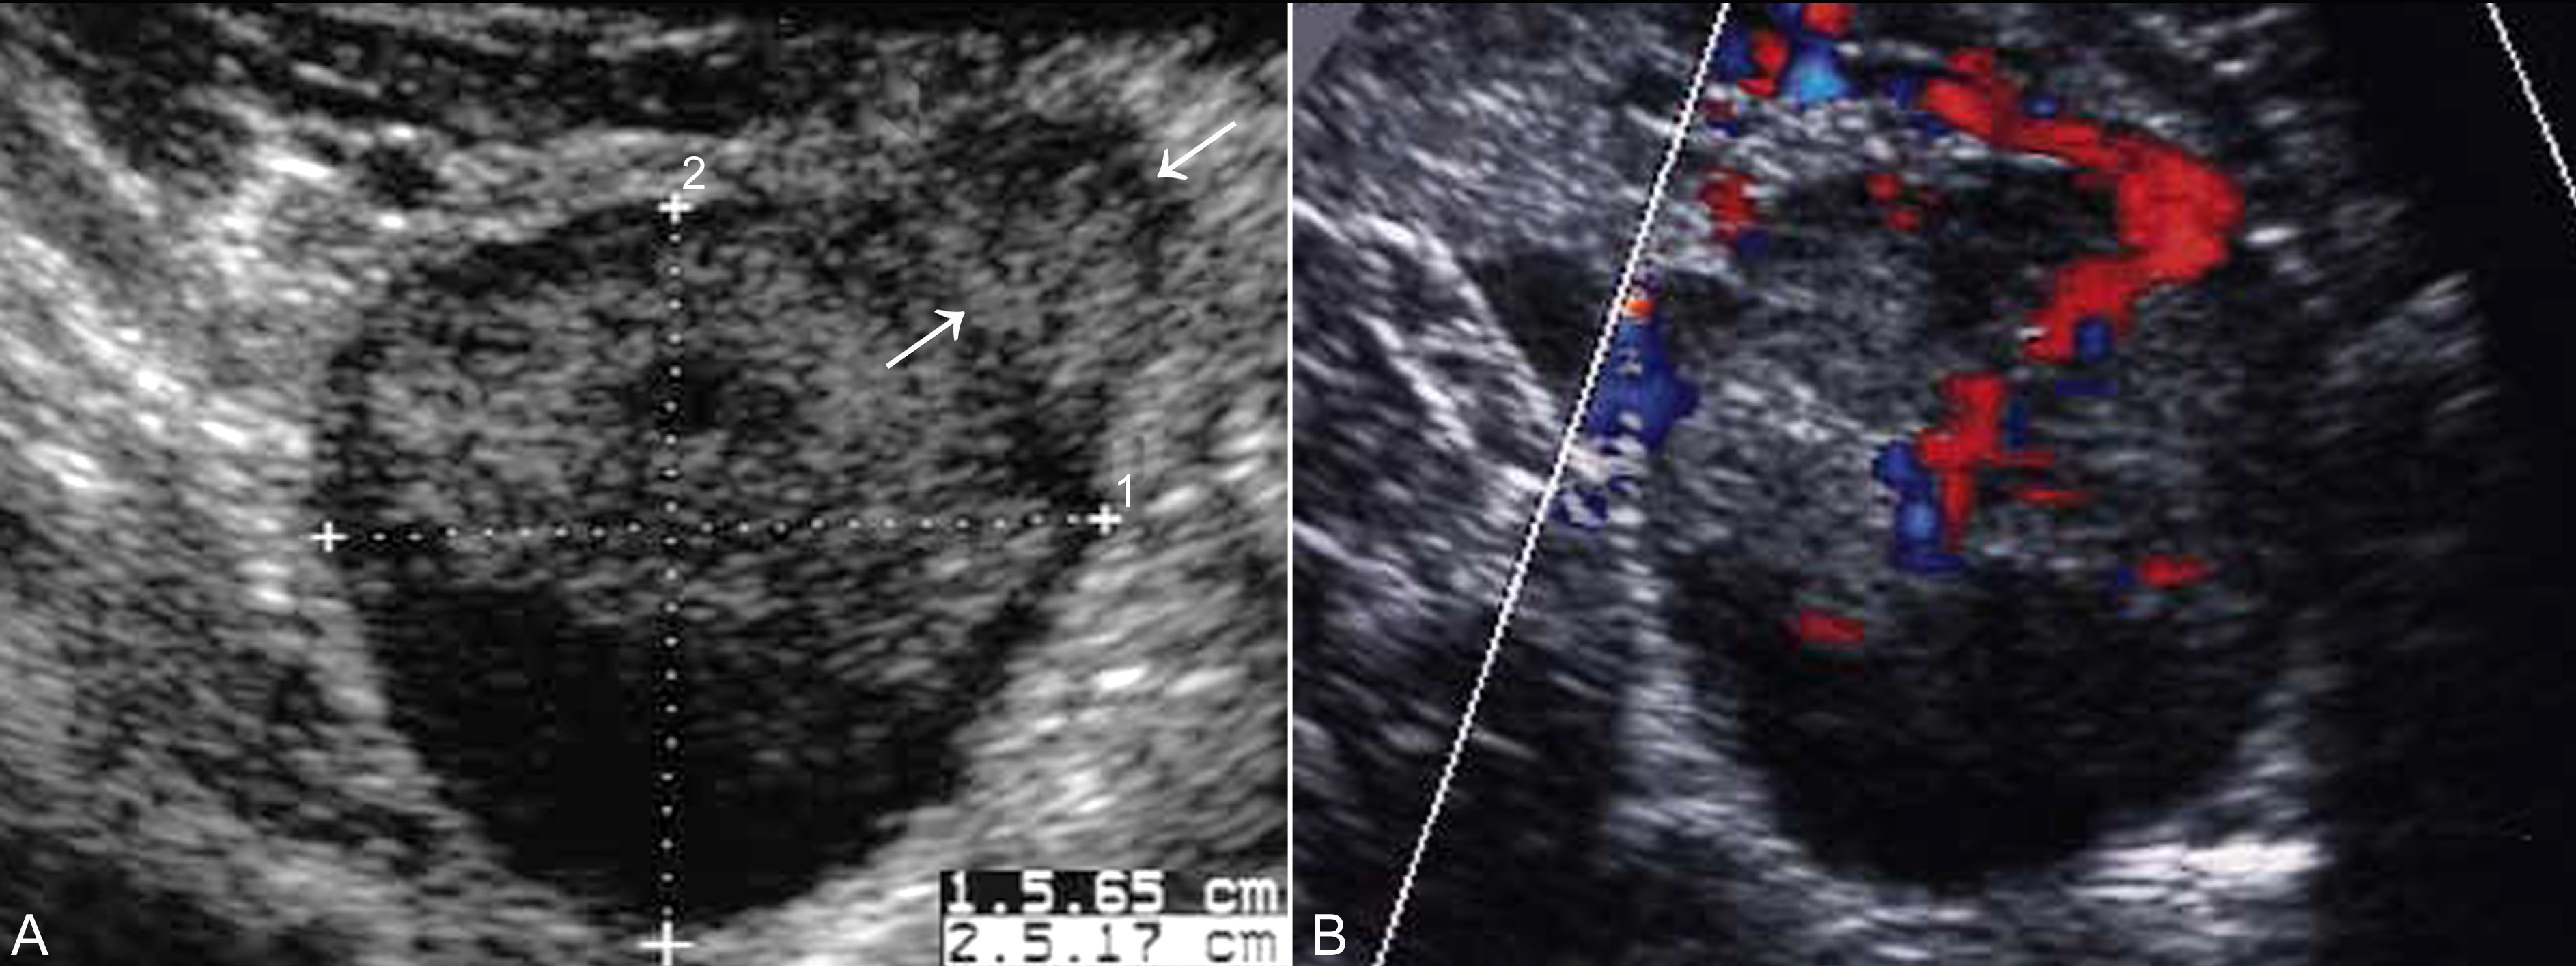

3.黄体瘤 妊娠黄体瘤(luteomas of pregnancy)又称妊娠黄素瘤,是妊娠期少见卵巢瘤样病变,多发生在妊娠3个月后,至2014年,文献报告的病例不超过200例。黄素瘤的发生可能与此时期的雄性激素水平升高有关,瘤体大小变化很大,大者直径可以达到20cm,平均直径6cm~8cm。在妊娠中后期孕妇可以出现嗓音低沉、面部*疮痤**、多毛、阴蒂肥大等雄激素作用,并可影响胎儿。超声检查显示为妊娠子宫一侧或双侧的实质性回声,形态多显示规则,内部显示为均匀或不均匀的的实质性回声(图2),内部有时可显示分隔征象;当黄体瘤内部有出血时可显示不均匀的回声;CDFI检查有时可以显示血管进入瘤体内(图3),有时可显示内部丰富的血流信号。由于超声显像检查可以发现合并腹水,孕妇血液检查有AFP和CA25升高,但同时合并的血液雄激素的升高以及孕妇男性化的表现可以提示卵巢黄素瘤。分娩后黄素瘤即开始缩小,随着体内激素水平的逐渐恢复,多数在分娩后三个月左右完全消失。

图3黄体瘤:A显示卵巢(箭头)一侧不均匀实性回声;B显示较粗的血管进入瘤体